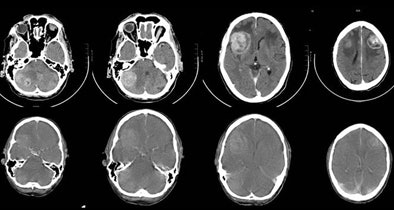

| Comparison of dedicated CT of the brain (CT1) versus the CT component of PET/CT (CT2) shows no statistically significant difference between these two CT scans in detecting malignant brain lesions, despite the fact that the quality of the CT of the brain in the PET/CT study is inferior. |